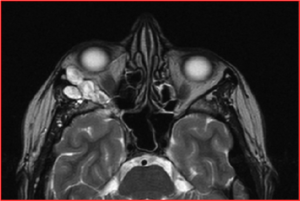

Die Endokrine Orbitopathie (EO) ist eine entzündliche Erkrankung der Augenhöhle, die meist zusammen mit einer Schilddrüsenüberfunktion im Rahmen einer Morbus Basedow Erkrankung auftritt. In etwa 80% der Fälle treten beide Erkrankungen zugleich innerhalb von wenigen Monaten auf, Teilweise tritt die Endokrine Orbitopathie jedoch auch erst Jahre später auf.

Die Entzündung betrifft die Bindegewebe und Augenmuskeln in der Augenhöhle. Die Endokrine Orbitopathie kann sehr unterschiedlich verlaufen. Die Beschwerden und auch die Therapiemöglichkeiten unterscheiden sich in der frühen entzündlichen Phase (aktive Phase) und der späten, nicht-entzündlichen Phase (inaktive Phase).

Beschwerden der Endokrinen Orbitopathie sind:

- Entzündungszeichen wie: Schwellung, Rötung, Schmerzen der Lider und der Bindehaut, Druckgefühl hinter dem Augapfel, Schmerzen bei Augenbewegung

- Hervortreten der Augäpfel durch entzündliche Schwellung des Bindegewebes und der Augenmuskeln

- Schielstellung der Augen mit Doppelbildbeschwerden

- Benetzungsstörungen der Hornhaut durch einen inkompletten Lidschluss und eine beeinträchtigte Tränensekretion können zu einem Fremdkörpergefühl, Verschwommensehen und erhöhter Lichtempfindlichkeit führen

- Vergrößerung der Lidspalte durch eine Verkürzung des Lidhebermuskels

- Sehnervenkompression durch erhöhten Druck in den Augenhöhlen mit Farbsehstörungen und Gesichtsfeldausfällen

Die Therapie in der aktiven Phase hat eine Rückbildung der entzündlichen Veränderungen zum Ziel. Häufig erfolgt eine Behandlung mit Cortison und anderen Medikamenten, teilweise auch eine Bestrahlungstherapie. Bei einer schnellen Sehverschlechterung kann auch in der aktiven Phase eine operative Entlastung der Augenhöhle zur Rettung der Sehfunktion notwendig werden.

In der inaktiven Phase werden die Beeinträchtigungen behandelt, die nach der Abheilung der entzündlichen Prozesse zurückbleiben können. Hierzu zählt insbesondere die Behandlung des bzw. der vorstehenden Augen (Exophthalmus). Im weiteren Behandlungsverlauf können auch Operationen zur Verbesserung von Doppelbildern und Lidschlussstörungen notwendig werden.

In unserer Neurochirurgischen Abteilung bieten wir angepasst an den jeweiligen Patienten Entlastungsoperationen der Orbita über alle Zugangswege einschließlich transnasal endoskopischer minimal invasiver Wege an. Besonders gute klinische Behandlungserfolge haben wir gerade bei Patienten mit starkem Exophthalmus durch Entlastungen der Orbita über einen transkraniellen Zugangsweg.

Diese Methode verbindet gegenüber den anderen Behandlungsoptionen insbesondere die Vorteile einer sehr großvolumigen Entlastung mit einem sehr geringen Risiko für das neue Auftreten oder die Verschlechterung von Doppelbildern. Auf eine Entfernung von Fettgewebe aus der Orbita, die auch mit dem Risiko einer Beeinträchtigung der Augenmuskeln und- nerven verbunden ist kann hierbei in der Regel ebenfalls verzichtet werden.

Deutliche Rückbildung des Vorstehens eines Auges (Exophthalmus) bei beidseitiger Endokriner Orbitopathie (im Bild linkes Auge behandelt). Die Knochen (im Bild weiß) der Orbitawand wurden hierzu teilweise geöffnet. Im weiteren Verlauf erfolgte auch eine Behandlung der anderen Seite. Die Sehfunktion der Patientin hat sich im Verlauf wieder normalisiert.